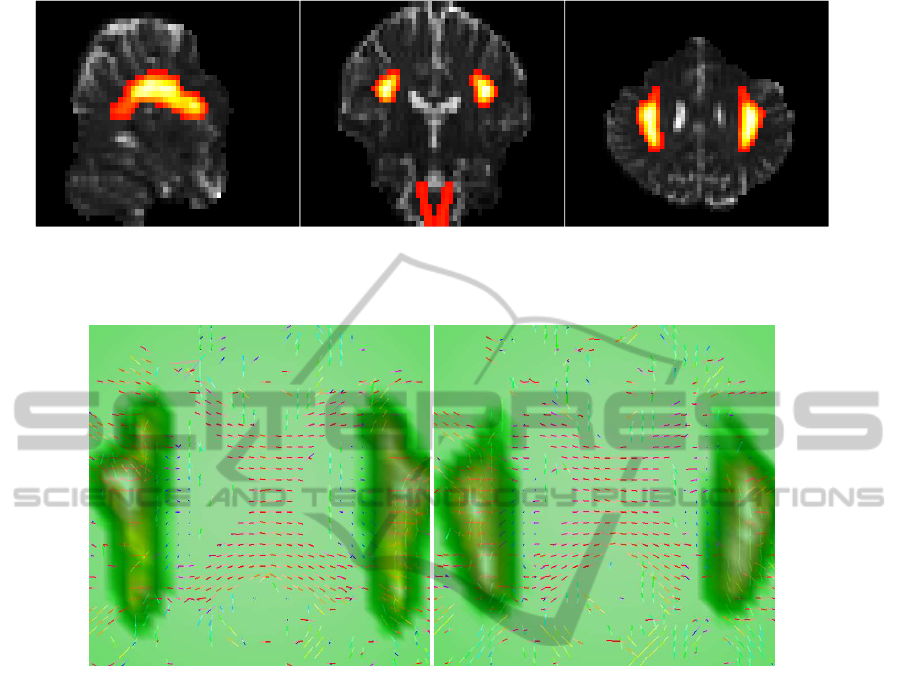

We believe that the directional statistics technique

proposed in this work offers significant increases in

sensitivity for anatomical analysis over traditional ap-

proaches. We intend to build on the quantitative and

qualitative information provided by the proposed di-

rectional statistics approach to support the study of

fiber tract architecture in the brain. In particular, this

information may be explored to build robust prob-

abilistic tractographic algorithms for complex fiber

configurations.